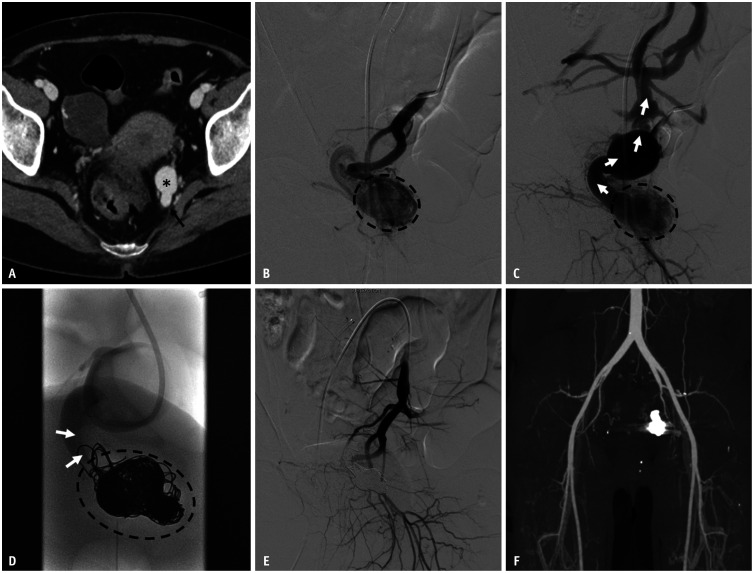

Materials and methods: A retrospective study was performed on 13 patients (median age, 43 years, range 20-62 years, 7 males) who underwent transvenous coil embolization for Type IIa pelvic AVM (characterized by multiple arterioles shunting to focal venous segments of a single draining vein) without the use of additional liquid embolic agents from March 2017 to February 2023. Treatment outcomes were analyzed based on clinical evaluations, post angiography findings, and follow-up CT.

Results: Fourteen procedures were performed on 13 patients. Except in one patient, all treatments were completed in a single session. Transvenous access was employed in 10 procedures, whereas direct puncture was used in four sessions. The embolization procedures used an average of 55.7 ± 58.5 coils (range, 7-238) and lasted an average of 127.3 ± 39.5 minutes. The technical success rate was 92.9% (of 13/14). All patients reported symptom improvement. Follow-up CT scans showed complete occlusion of the AVM without recurrence in ten of the 13 patients. There was one minor adverse event: a small retroperitoneal hemorrhage, likely related to direct puncture, which resolved spontaneously. No other adverse events were observed.